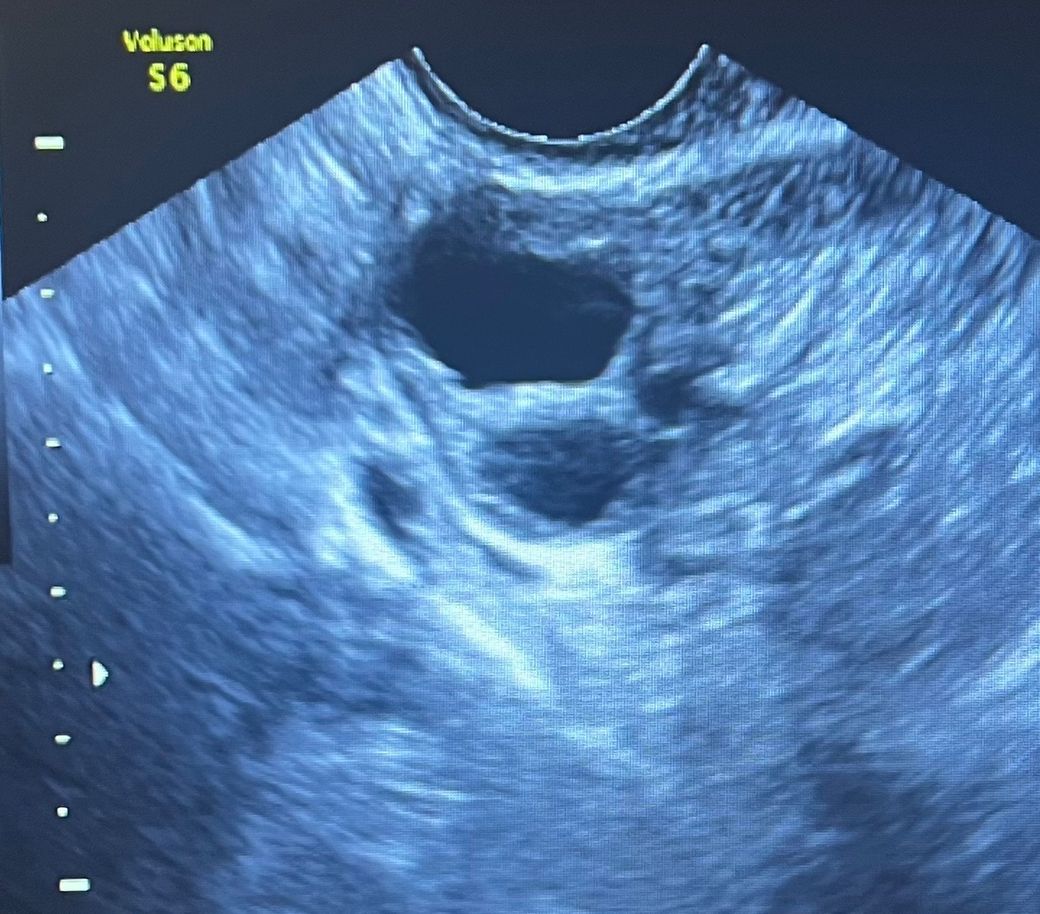

출산 후 검진을 하는데 난소낭종이 생겼다고 하더라구요.

그땐 사이즈가 작았지먼 석회가 꼈다고

초음파도 안좋아서 난소암검사를 다시 진행하고 .. 결과가..